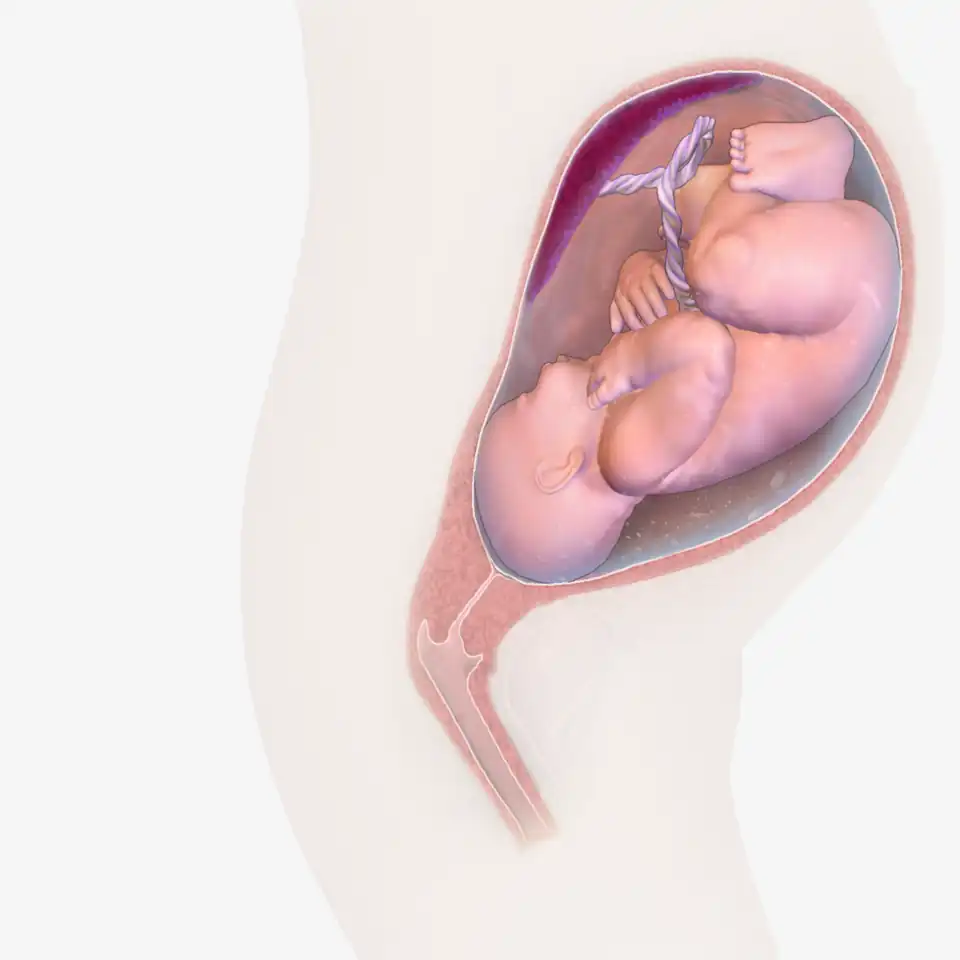

Effects of nicotine on fetal development diagram

Possible effects of nicotine on the developing human fetal brain

Nicotine exposure during pregnancy can harm fetal brain development.[14]

Fetal development

There is accumulating research concerning the negative effects of nicotine on prenatal brain development.[notes 5][110] Vaping during pregnancy can be harmful to the fetus.[111] There is no supporting evidence demonstrating that vaping is safe for use in pregnant women.[104] Nicotine accumulates in the fetus because it goes through the placenta.[112] Nicotine has been found in placental tissue as early as seven weeks of embryonic gestation, and nicotine concentrations are higher in fetal fluids than in maternal fluids.[15] Nicotine can lead to vasoconstriction of uteroplacental vessels, reducing the delivery of both nutrients and oxygen to the fetus.[113]

As a result, nutrition is re-distributed to prioritize vital organs, such as the heart and the brain, at the cost of less vital organs, such as the liver, kidneys, adrenal glands, and pancreas, leading to underdevelopment and functional disorders later in life.[113] Nicotine attaches to nicotinic acetylcholine receptors in the fetus brain.[90] The stage when the human brain is developing is possibly the most sensitive time period to the effects of nicotine.[104] When the brain is being developed, activating or desensitizing nicotinic acetylcholine receptors by being exposed to nicotine can result in long-term developmental disturbances.[90]

Prenatal nicotine exposure has been associated with dysregulation of catecholaminergic, serotonergic, and other neurotransmitter systems.[15] Prenatal nicotine exposure is associated with preterm birth,[76] stillbirth,[76] sudden infant death syndrome,[104] auditory processing complications, changes to the corpus callosum,[105] changes in brain metabolism,[106] changes in neurological systems,[104] changes in neurotransmitter systems,[106] changes in normal brain development, lower birth weights compared to other infants,[104] and a reduction in brain weight.[108]

A 2017 review states, "because nicotine targets the fetal brain, damage can be present, even when birth weight is normal."[90] A 2014 US Surgeon General report found "that nicotine adversely affects maternal and fetal health during pregnancy, and that exposure to nicotine during fetal development has lasting adverse consequences for brain development."[14] Nicotine prenatal exposure is associated with behavioral abnormalities in adults and children.[107] Prenatal nicotine exposure may result in persisting, multigenerational changes in the epigenome.[3]